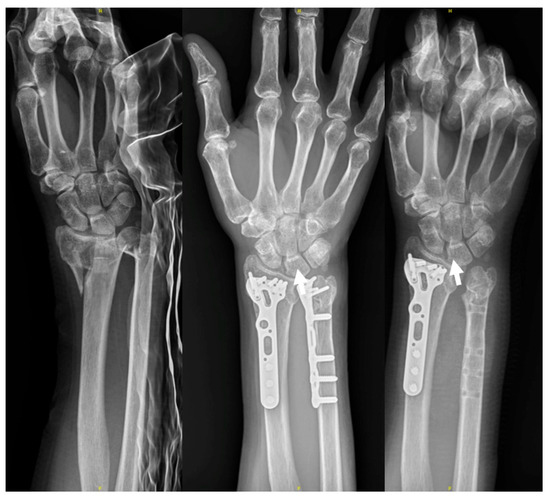

Figure 1.

The figures showed intraoperative images of initial fracture fixation through the modified dual window approach. (A) Straight skin incision is made between the interval of flexor carpi radialis (FCR) and palmaris longus (PL), which is around 8–9 cm; (B) ORIF of the radius was conducted through the lateral window. (C) ORIF of the ulna was conducted through the medial window. (D) fluoroscopy: anteroposterior view after final fixation of the DRF; check the alignment of the DUF. (E) fluoroscopy: DUF under ORIF with a point-to-point reduction clamp; the skin incision is made between the interval of FCR and PL.